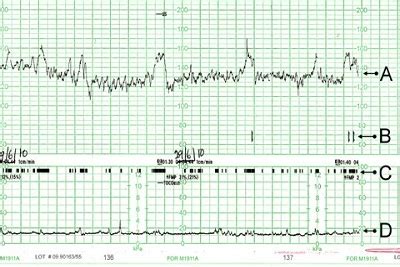

Pomemben vidik spremljanja v tem obdobju je ocena plodovih gibov. Do približno 32. tedna nosečnosti, ko plod še razpolaga z dovolj prostora, so gibi izraziti. Ko pa prostor postane omejen, se gibanje lahko spremeni ali zmanjša. Če nosečnica zazna bistveno zmanjšanje ali odsotnost plodovih gibov (manj kot 10 gibov dnevno), je nujen pregled z ultrazvokom in kardiotokografijo (CTG) za preveritev stanja ploda.

V zadnjem mesecu nosečnosti se intenzivno pogovarjamo o porodu. V 37. in 39. tednu nosečnosti se lahko opravi brezplačna kontrola kondicije ploda s kardiotokografijo (CTG) in ultrazvočno preiskavo, ki vključuje oceno plodovnice, zrelosti posteljice in oskrbe ploda s kisikom preko Dopplerja popkovničnih žil.

Pri 37., 38., 39. in 40. tednu nosečnosti se nadaljujejo rutinski pregledi, ki vključujejo merjenje krvnega tlaka, telesne teže in urina, ter pogovor o počutju nosečnice. V tem času se lahko opravi tudi ginekološki vaginalni pregled za oceno zrelosti materničnega vratu. Če je maternično ustje zaprto in nezrelo, se nosečnico običajno preda v varstvo do poroda osebni ginekolog. V primeru, da se porod še ne začne, se CTG posnetki in ultrazvočne meritve količine plodovnice izvajajo na vsake 2-3 dni do 41. tedna nosečnosti.